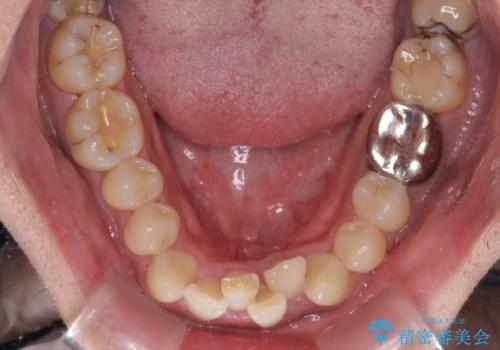

重なって磨きにくい上下の前歯 ワイヤー装置での抜歯矯正

- 前歯のデコボコを改善したいと来院された患者様です。

口元の突出感はないものの、上顎前歯のデコボコが著しかったため、上下顎左右小臼歯4本を抜歯することとしました。

上下の正中位置を改善するため、右下は第一小臼歯を、その他は第二小臼歯を抜歯することとしました。